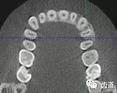

1)根管治療中牙膠尖充填在CBCT中的影像

2)根管測量

2、多生牙

多生牙的定位